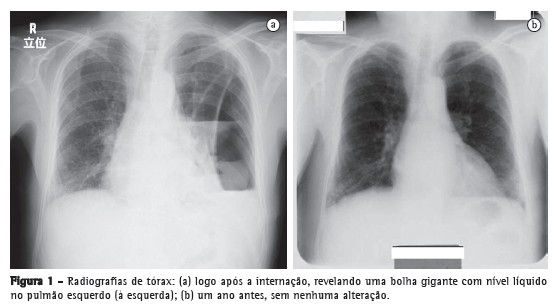

Relato de casoUm homem de 79 anos de idade buscou tratamento no pronto-socorro devido a um histórico de 3 meses de febre persistente, dor torácica e fadiga geral. Apresentava carga tabágica de 60 anos-maço e fizera uso pesado de saquê japonês (180 mL/dia) durante os últimos trinta anos. Os exames laboratoriais realizados indicaram a presença de inflamação grave, e a radiografia de tórax revelou uma bolha gigante de 24 cm de diâmetro no pulmão esquerdo (Figura 1a). Segundo o próprio paciente, não apresentava histórico de alterações radiográficas, e seu último check-up médico, realizado no ano anterior, não revelara anormalidades (Figura 1b). A TC de tórax revelou que a bolha continha líquido e media 4.5 × 17 × 24 cm (Figura 2). O paciente foi diagnosticado com abscesso pulmonar e foi internado em nosso hospital.

Embora tenham sido propostas diversas teorias a respeito da etiologia de bolhas gigantes, a origem dessas bolhas ainda é controversa. Sugeriu-se que bolhas gigantes ocorrem devido ao suposto "mecanismo valvular",(3) à oclusão brônquica ou à transformação das artérias pulmonares e brônquicas.(7) Na verdade, o único outro mamífero no qual o enfisema pulmonar ocorre espontaneamente é o cavalo, e um estudo experimental em cavalos mostrou que a oclusão da artéria brônquica desempenha um papel importante.(2) A maioria dos investigadores concorda que lesões degenerativas fazem com que as paredes alveolares percam sua elasticidade.(2) À medida que as paredes se expandem, os alvéolos ficam maiores e alguns se rompem, permitindo o escape de ar para dentro do parênquima pulmonar, resultando na formação de blebs e bolhas.(2) Fain et al. atribuíram a formação de bolhas gigantes ao fumo, que diminui o fluxo sanguíneo para os alvéolos.(2) No caso apresentado aqui, a bolha gigante pareceu ter crescido rapidamente, visto que nenhuma alteração havia sido encontrada durante o check-up médico conduzido no ano anterior. Presumimos que o mecanismo valvular relacionado ao tumor no brônquio inferior esquerdo tenha promovido o crescimento da bolha.